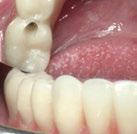

La exploración intraoral (figuras 4 a 8) revela una Clase II molar y canina completa, líneas 1/2 dentarias superior 0,5 mm e inferior 1 mm ambas desviadas hacia la derecha, los incisivos superiores excesivamente protruidos y vestibulizados (seguramente debido a la interposición del labio inferior), resalte de 13 mm y sobremordida 2/3 de corona. La discrepancia oseodentaria

inferior es de -3,5 mm y la curva de Spee de 4 mm.